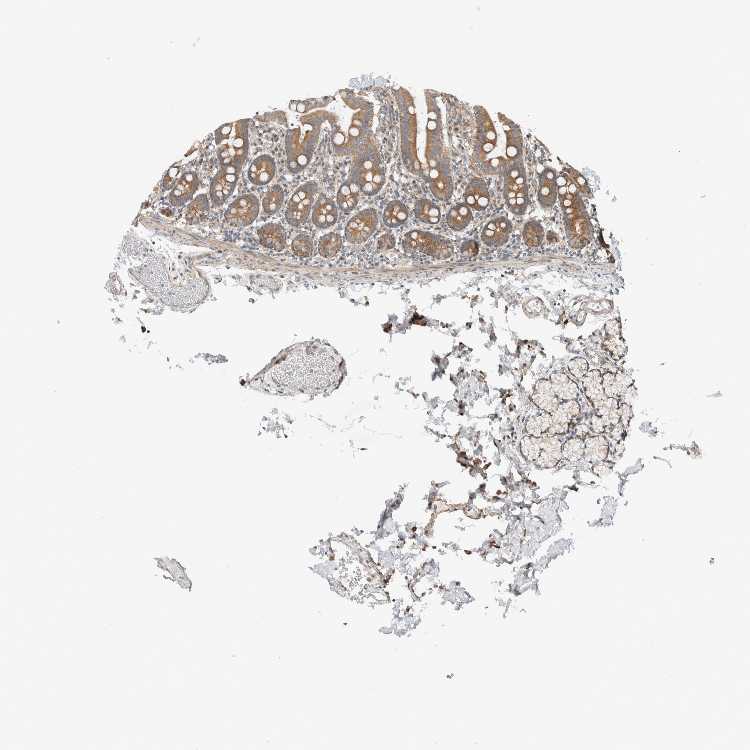

TISSUE PRIMARY DATA DUODENUM Show tissue menu

DUODENUM - Antibody stainingi

Antibody staining in the annotated cell types in the current human tissue is reported as not detected, low, medium, or high, based on conventional immunohistochemistry profiling in selected tissues. This score is based on the combination of the staining intensity and fraction of stained cells.

Each image is clickable and will lead to virtual microscopy that enables deeper exploration of all samples and also displays staining intensity scores, fraction scores and subcellular localization as well as patient and tissue information for each sample.

Antibody HPA024093

Glandular cells Medium